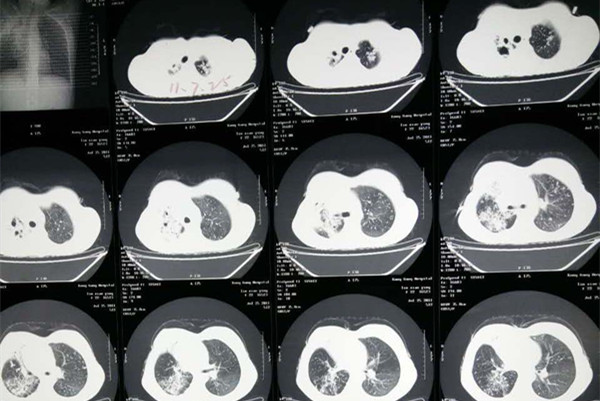

那么发现肺结核耐药后具体如何诊断呢?诊断耐药肺结核,除了常规的痰涂片和胸部影像学检查外,还要进行痰培养和药物敏感性试验确诊;目前采用分子生物学检测技术可快速诊断耐药肺结核。